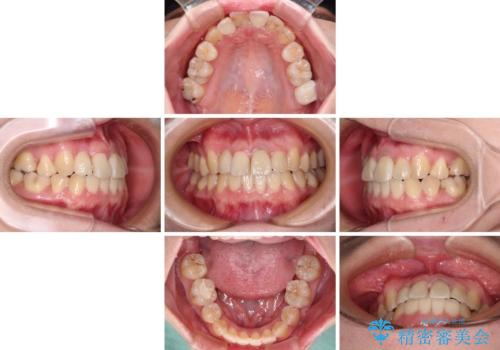

虫歯治療ついでに歯並びの後戻りを改善 インビザラインによる矯正治療

根管治療を行った歯はクラウンによる補綴治療が必要となりますが、高校生の頃に行った矯正治療の後戻りも気になるとのことで、補綴治療を行う前に矯正治療を行うこととしました。

後戻りは軽度であり、インビザラインにて歯列を整え、その後にオールセラミッククラウンにて補綴治療を行うこととしました。

ご家庭やお仕事の都合で通院が途絶えた時期があり、治療は長期間となりましたが、無事に終えることができました。